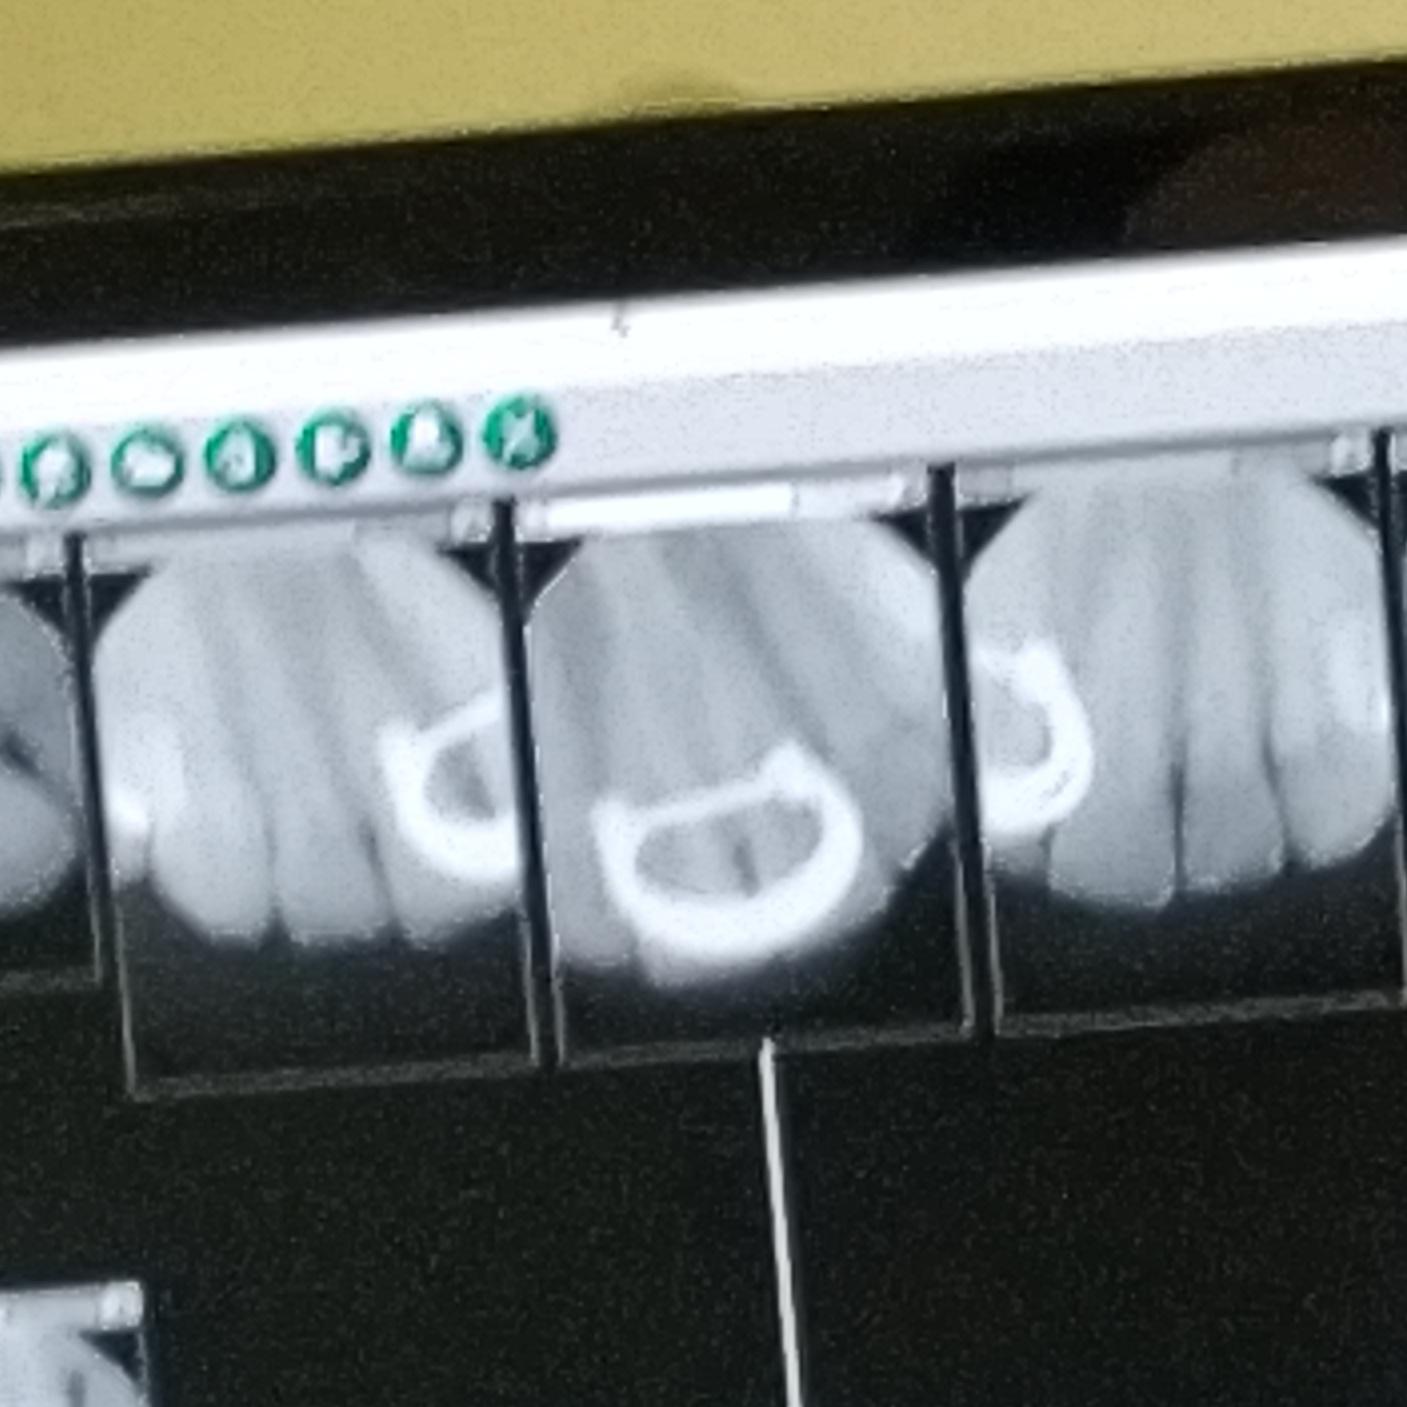

You can see my nose ring in my dental xray. r/mildlyinteresting Nose Ring Dental X Ray For intra oral ones then they can be left in. As for record keeping, a dentist may. However its up to the clinician to. Contact us for costs and all types of x. For extra oral they ideally should be taken out but. The nose ring will appear on the xray in an area that can block a possible tooth. Nose Ring Dental X Ray.

got my first xray with all my piercings in taken at the orthodontist Nose Ring Dental X Ray However its up to the clinician to. As for record keeping, a dentist may. Contact us for costs and all types of x. For extra oral they ideally should be taken out but. For intra oral ones then they can be left in. The nose ring will appear on the xray in an area that can block a possible tooth. Nose Ring Dental X Ray.

Got an X ray at the dentist and couldn’t take out my nose ring, so now Nose Ring Dental X Ray However its up to the clinician to. The nose ring will appear on the xray in an area that can block a possible tooth image. For intra oral ones then they can be left in. As for record keeping, a dentist may. For extra oral they ideally should be taken out but. Contact us for costs and all types of. Nose Ring Dental X Ray.

The way my nose ring and lip ring show up in my dental Xrays r Nose Ring Dental X Ray For intra oral ones then they can be left in. However its up to the clinician to. The nose ring will appear on the xray in an area that can block a possible tooth image. As for record keeping, a dentist may. For extra oral they ideally should be taken out but. Contact us for costs and all types of. Nose Ring Dental X Ray.

You can see my nose ring in my dental xray r/mildlyinteresting Nose Ring Dental X Ray For intra oral ones then they can be left in. As for record keeping, a dentist may. The nose ring will appear on the xray in an area that can block a possible tooth image. However its up to the clinician to. For extra oral they ideally should be taken out but. Contact us for costs and all types of. Nose Ring Dental X Ray.

Was told I could keep my nose ring on during xrays... Got a laugh out Nose Ring Dental X Ray For extra oral they ideally should be taken out but. The nose ring will appear on the xray in an area that can block a possible tooth image. Contact us for costs and all types of x. As for record keeping, a dentist may. However its up to the clinician to. For intra oral ones then they can be left. Nose Ring Dental X Ray.